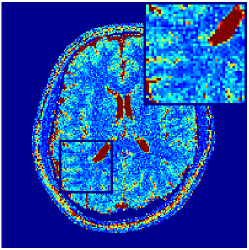

Two sets of experiments were conducted here: first, we used the 2D and 3D acquisition sequences for scanning a healthy volunteer’s brain (real-world acquisitions). Figures 6 and 7 display the parametric maps reconstructed from 2D spiral and radial readouts. We computed the T1, T2 and proton density (PD) maps using baseline reconstruction algorithms ZF, VS, LR, FLOR, AIR-MRF and our proposed LRTV. While baselines use DM either for quantitative inference or also during reconstruction (i.e. AIR-MRF), we further compare the DM-free LRTV’s performance when cascaded to DM, KM and MRFResnet for quantitative inference. For the 3D spiral acquisitions we compared LRTV and its closest competitor VS in Figure 8. Outcomes from other tested algorithm are displayed in the supplementary materials (Figure S5). Since FLOR does not use dimensionality-reduction, our system ran out of memory during 3D reconstruction; hence results are not reported in this case.

VI-E1 Discussion

The LRTV-DM and LRTV-MRFResnet perform on par, and both outperform all tested baselines for reconstructing T1, T2 and PD maps in all acquisition schemes. This can be observed both visually in Figures 6, 7, 8, S2 and S3, and quantitatively in Table IV across all tested metrics. Other baselines were unable to successfully remove the under-sampling artefacts in TSMIs, and these errors propagated to the parameter inference phase and resulted in inaccurate maps. Temporal-only priors incorporated within LR are shown insufficient to regularise the inverse problem and LR sometimes (e.g. 2D spiral acquisitions) can admit solutions with even stronger artefacts than the model-free ZF baseline. This issue was previously studied for other non-Cartesian MRF readouts that similar to our spiral/radial trajectories, miss to sample the corners of the k-space in all timeframes (see section 2.2.2 and figure 2 in [19]). In the absence of reference for the k-space corners information, the LR iterations despite minimising the objective can converge to solutions with high-frequency artefacts, as visible in the computed maps. This highlights the need for adding an appropriate spatial-domain regularisation. FLOR reduces the LR’s artefacts but this improvement is limited because the suggested nuclear norm penalty does not incorporate an explicit spatial regularisation. Further for reducing artefacts, FLOR can introduce an undesirable bias in the computed T1/T2 maps e.g. see error maps in Figures S2 and S3. The non model-based VS baseline incorporates spatial regularisation and results in spatially smoother maps than ZF and LR, but it is unable to output artefact-free images. Further and consistent with our in-vitro experiment, we observe that VS overestimates the T2 values (e.g. in White and Grey matter regions) in tested 2D acquisitions i.e. the spatial regularisation trades off agains the quantification accuracy. The model-based AIR-MRF adds spatial regularisation through 2D/3D low-pass Gaussian filters however this trades off the sharpness of the computed maps and can increase the errors at the tissue boundaries (we searched Gaussian spreads that keep the blurs and high-frequency artefacts minimal). For our acquisition readouts, Gaussian filters performed better than disk filters of [19] for avoiding strong Gibbs artefacts. On the other hand, the spatiotemporally regularised LRTV greatly improves the TSMI reconstructions i.e. 4 dB enhancement compared to the closest competitor baseline (Table IV). This enables computing accurate and aliased-free multi-parametric inference using DM or the DM-free learning-based alternative MRFResnet as visible in Figures 6, 7, 8, S2 and S3. MRResnet and DM score competitive quantitative inference results i.e. T1 and T2 MAPE less than 5% and 9%, respectively (Table IV). KM also outputs comparably accurate T1 maps, however this shallow learning model despite having a model size larger than MRFResnet, is unable to learn accurate T2/PD quantification and it results in poor estimated maps, consistent with our observations in section VI-C.